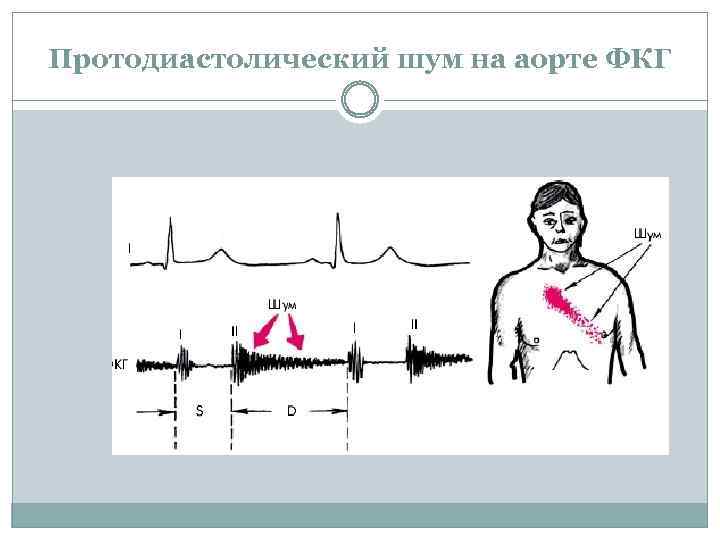

Аускультация сердца На верхушке ослаблен Iтон (отсутствие периода замкнутых клапанов) На аорте – ослаблен II тон (не смыкание полулунных клапанов) Протодиастолический шум на аорте и в з. Боткина Нередко III тон Шум мезодиастолический на верхушке ш. Флинта (относительный стеноз митрального клапана)

Протодиастолический шум на аорте ФКГ